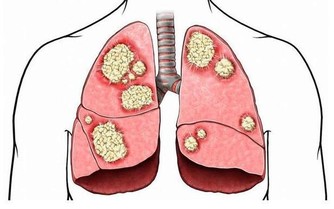

生老病死是人之常情,當人的年齡逐漸增大之後,身體的各個器官就開始漸漸衰老,生命也會漸漸失去活力。人在45歲之後。隨著我們的身體曰益衰老,心臟向全身輸送血液的效率也開始降低。這是因為血管逐漸失去彈性,動脈變硬或者出現阻塞。造成這些變化的原因是脂肪在冠狀動脈堆積,輸送到心臟的血液減少,有時會引起心絞痛。45歲以上的男性和55歲以上的女性心髒病發作的概率較大。